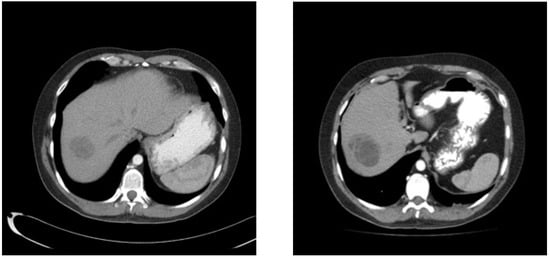

A 30-year-old patient awaiting a living-related donor renal transplant for chronic renal failure (creatinine 571 umol/L) related to reflux nephropathy presented to the local emergency room with right upper quadrant pain. Laboratory investigations revealed elevated liver function tests with hepatomegaly on abdominal ultrasound and multiple hepatic masses suspicious for metastasis. Subsequent computed tomography of the chest, abdomen, and pelvis confirmed multifocal hepatic lesions (Figure 1), periportal lymph nodes, a 4-mm nonspecific left lower lobe lung lesion, sclerotic lesions of the ribs, and a large mass in the left scrotum consistent with a testicular cancer (Figure 2). Bone scan also demonstrated sclerotic lesions in the seventh thoracic vertebrae, sternum, and the left iliac bone. Physical exam confirmed a large right testicular mass. His alpha fetal protein (AFP) was 62,777 umol/L (normal < 10), Beta-human chorionic gonadotropin (B-HCG) was 32 IU/L (normal < 1), and the lactic acid dehydrogenase (LDH) was 367 U/L (normal < 192).

Figure 1. Baseline unenhanced CT scan showing multiple liver metastases.